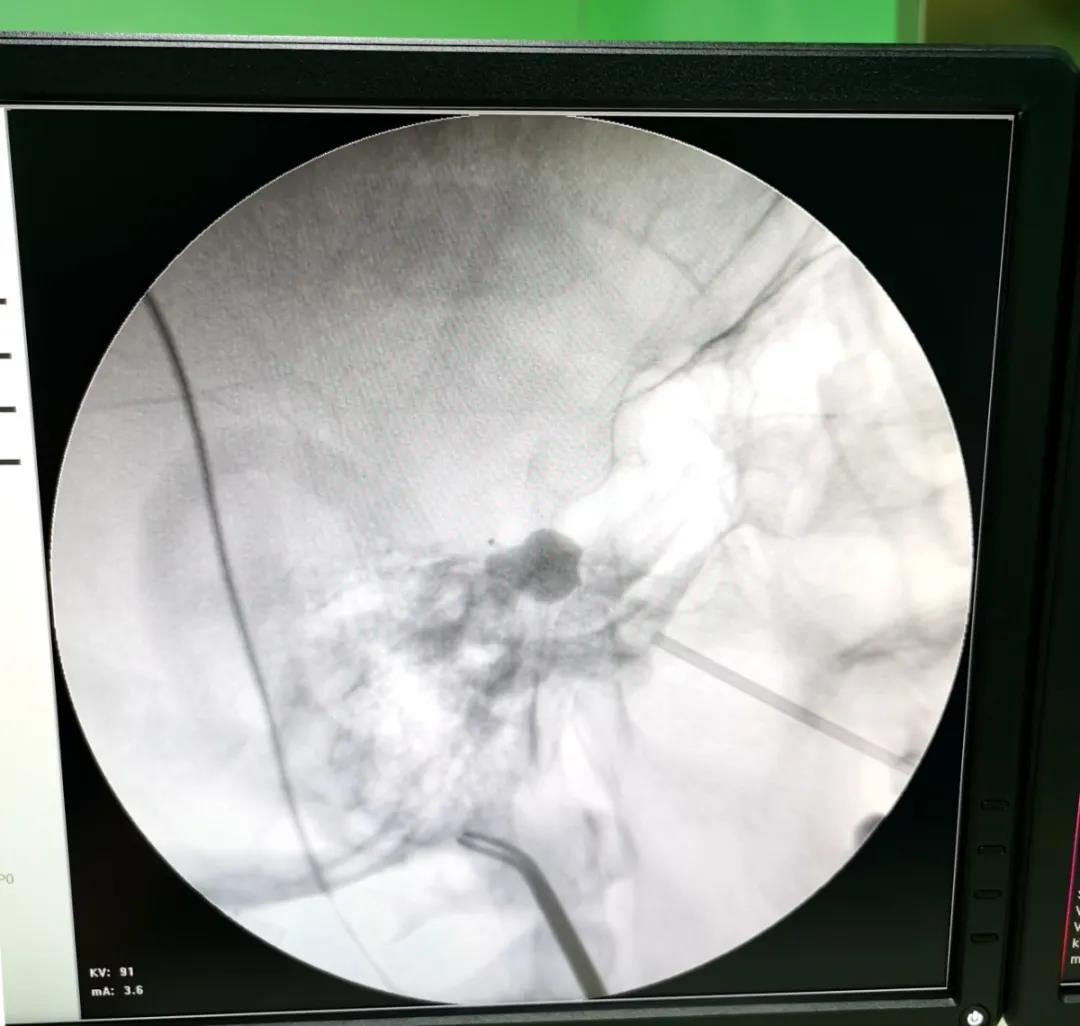

1月21日下午,我院心血管内科聯合新鄉醫學(xué)院第一附屬醫院神經(jīng)外科一病區成(chéng)功完成(chéng)一例三叉神經(jīng)半月節球囊壓迫手術,特邀一附院關慶凱副主任醫師前來主刀,在介入手術室等科室的配合下成(chéng)功爲患者解除了多年病痛,同時(shí)填補了我院在三叉神經(jīng)痛新技術領域的運用空白。

三叉神經(jīng)痛俗稱“天下第一痛”,是最常見的顱神經(jīng)疾病之一。三叉神經(jīng)痛呈刀割樣(yàng)疼痛,患者往往不敢刷牙、洗臉,痛苦不堪,嚴重影響生活質量。微球囊壓迫術作爲微創穿刺治療三叉神經(jīng)痛的重要手段,隻需通過(guò)針眼大小的創口放入穿刺針,經(jīng)口角外側用穿刺針穿刺經(jīng)卵圓孔達半月節,在半月節位置導入球囊,擴張微球囊持續壓迫3~5分鍾即可阻斷三叉神經(jīng)痛覺神經(jīng)傳導,達到治療目的。手術時(shí)間短,效果明顯,複發(fā)率低,術後(hòu)恢複快,此次手術爲該患者順利實施微球囊壓迫術,患者多年頑痛一朝解除,僅住院1-2天即康複出院。

上圖爲關慶凱副主任醫師與我院心血管内科醫護人員共同攜手打造新鄉醫學(xué)院第一附屬新華醫院三叉神經(jīng)痛微球囊壓迫術,新鄉醫學(xué)院第一附屬醫院神經(jīng)外科具有二十多年的三叉神經(jīng)診療經(jīng)驗,精通各種(zhǒng)治療方式,已取得經(jīng)治患者廣泛的認可和好(hǎo)評,歡迎廣大三叉神經(jīng)痛患者咨詢。